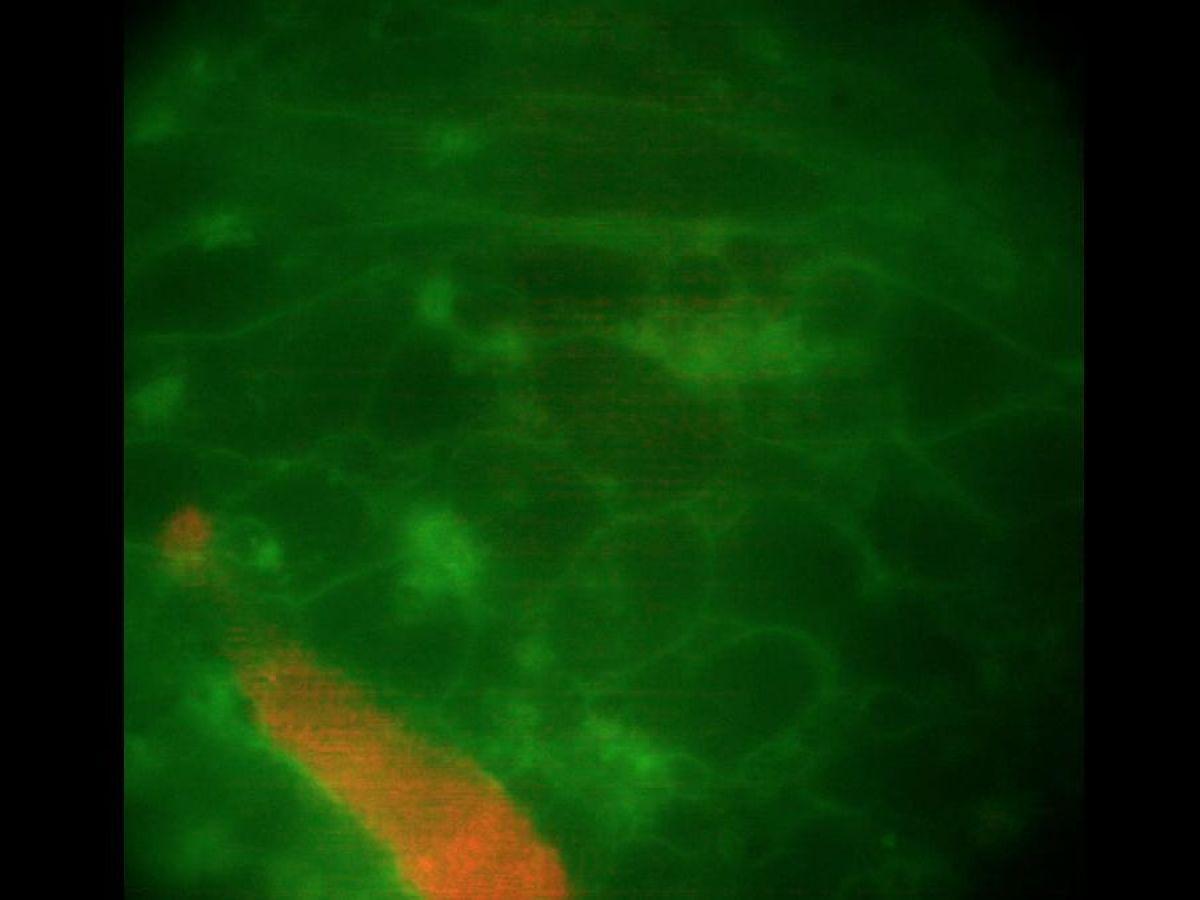

Les chercheurs ont alors découvert qu’une part importante (85 %) de ces macrophages établissaient des connexions électriques directes avec les cellules cardiaques voisines. En ayant recours à des marqueurs fluorescents, ils se sont aussi rendus compte que les macrophages pulsaient de manière synchronisée avec les cellules musculaires cardiaques, provoquant des battements visibles à l’œil nu.